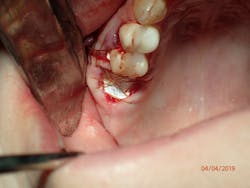

Therefore, if a patient has 5 mm of available bone height from the sinus floor, a maximum of 5 mm is prudent to expect from an indirect lift; therefore, an 8 mm to 10 mm implant is the ideal choice. The tapered iHex or MorsTorq implant provides safety when dealing with sinus areas, for three reasons. First, the taper helps prevent overinsertion toward the sinus cavity. Second, the abutment and transfer attached to the implant allows for more control. Finally, the rounded apex helps reflect the sinus floor without creating damage (figures 1-6).